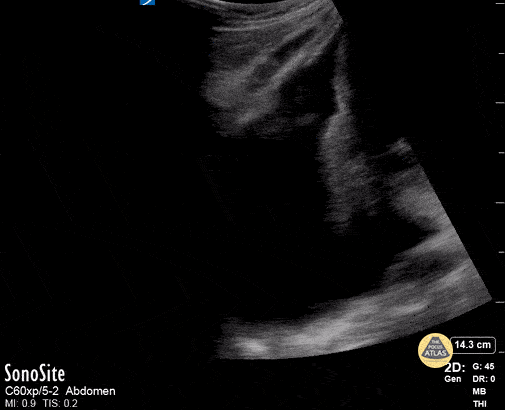

Peds-Lung - Large Pleural Effusion

Large pleural effusion in a teenager Contributor: Peter Gutierrez, MD, FAAP, Emory University School of Medicine/Children's Healthcare of Atlanta, @pocuspete